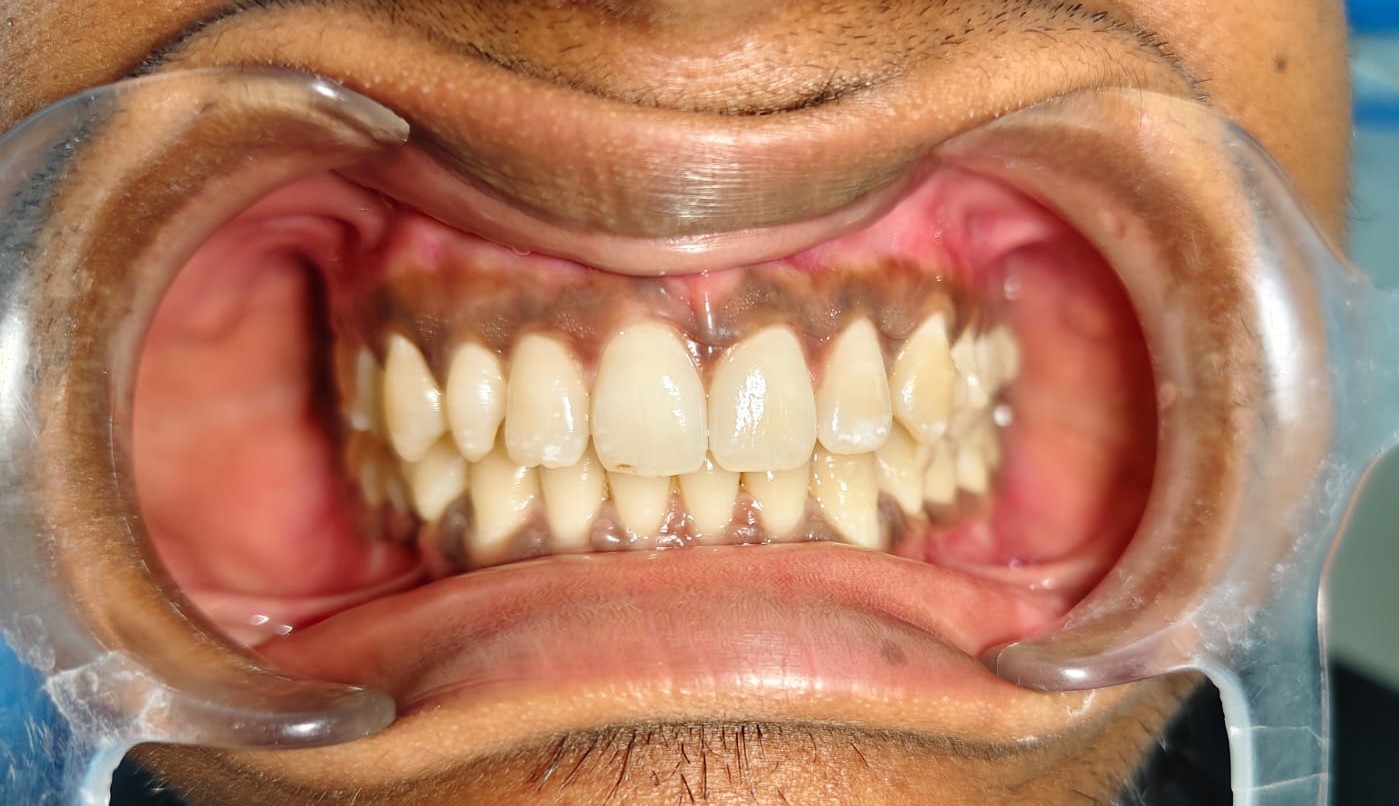

After/Before

See stunning smile transformation before and after